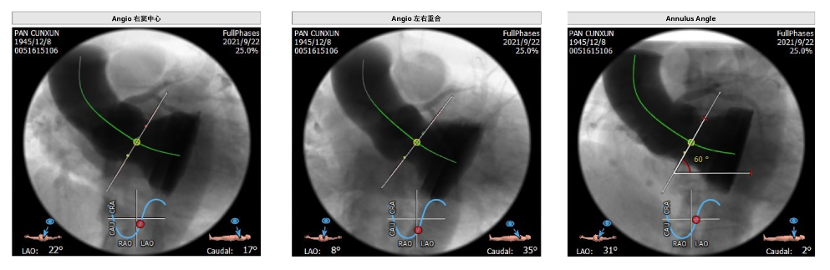

主动脉根部分析:三叶瓣,纯反流无钙化,窦部空间可,冠脉开口高,瓣环水平夹角60度,呈横位心。

根据CT测量分析选择植入30mm瓣膜。